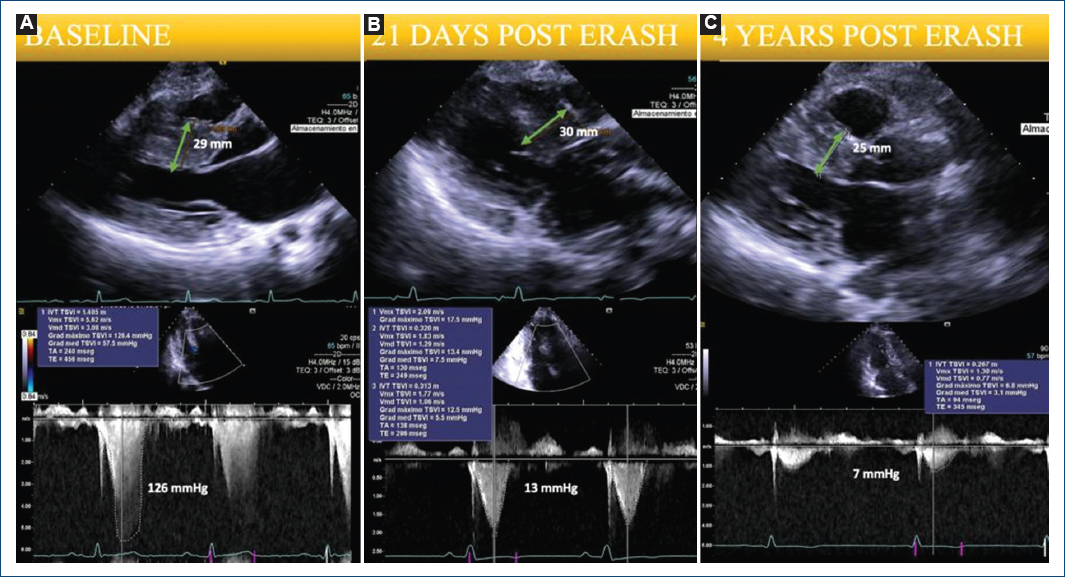

Figure 2 A: echocardiographic measurements of septal thickness and left ventricular outflow tract gradients performed under resting conditions before endocardial radiofrequency ablation of septal hypertrophy (ERASH) B: at 21 days of follow-up C: and 4 years post-ERASH.

After the procedure, the patient continued standard medication. In 2022, TTE showed an EF of 71%, an LVOT gradient of 9 mmHg, and mild SAM; in 2023, EF was 60%, an LVOT gradient of 7 mmHg, without SAM, and a wall/septum thickness of 9/25 mm on TTE, which indicates that the benefit and effectiveness of the procedure improved months later independently of the septum size (Fig. 2).

Studies have shown significant symptom improvement and sustained LVOT gradient reduction at a 6-month follow-up with ERASH7. Our patient's LVOT gradient was substantially reduced from 126 mmHg pre-procedure to 7 mmHg at a 4-year follow-up, with a resolution of SAM and symptoms.